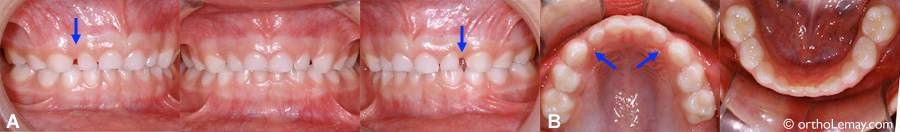

Exemples d’espaces primates dans la dentition humaine moderne

Exemple typique d’espaces ressemblant celui des primates présents dans une dentition non traitée en orthodontie chez une fille de 14 ans.

Présence d’espaces similaires aux espaces primates chez un homme de 23 ans non traité en orthodontie.

(A) Une partie de l’espace peut aussi être expliquée par les latérales qui sont légèrement étroites.

(B) Ces espaces sont présents depuis le dentition temporaire et sont stables. Ils ne se refermeront pas.